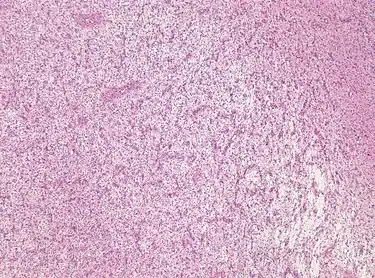

For further confirmation, the clinicians require biopsy and immunohistochemical staining of the resected tumor after surgery. The infiltrative AG cells display positive results for several immunostainings, especially the glial fibrillary acidic protein (GFAP) and epithelial membrane antigen (EMA).[1] Clinicians also observe a specific dot-like pattern from the stained EMA photomicrograph.[3] Other specific AG immunohistochemical tests include Ki-67 proliferative marker, neurospecific nucleoprotein (NeuN), protein 53, synaptophysin (Syn), oligodendrocyte transcription factor-2 (Olig-2) and creatine kinase (CK).[3] In the 2016 WHO classification of CNS tumors, AG is characterised as GFAP-positive, NeuN-positive and low Ki-67 proliferative rate with a perivascular growth pattern.[13]